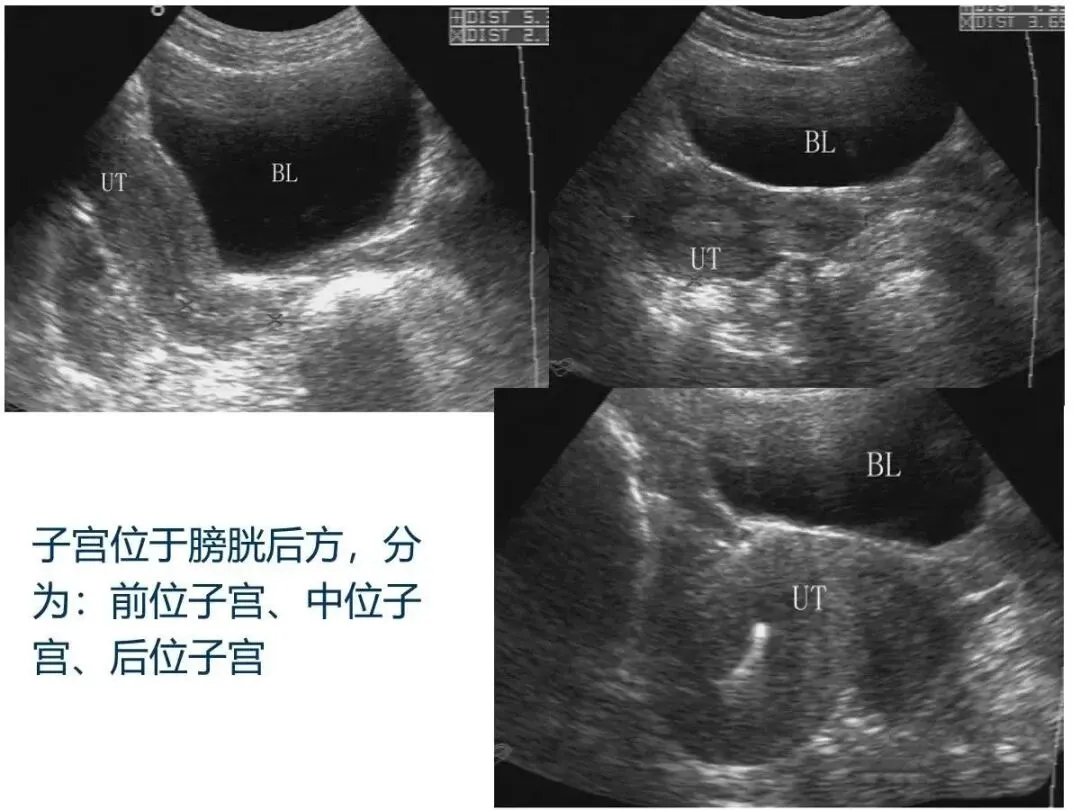

子宫位于骨盆中央,呈倒置的梨形,分为宫底、宫体、和宫颈。